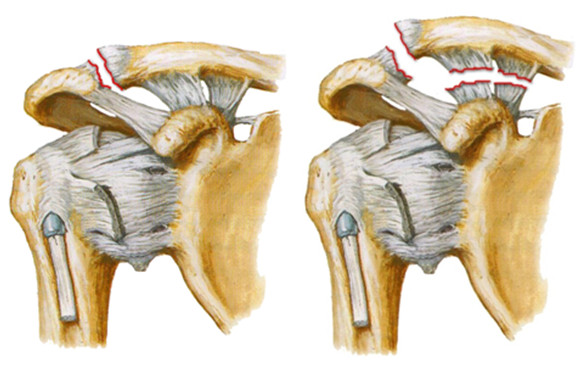

Конечно же, поскольку связок, прикрепляющихся к ключице несколько, то возможны различные варианты их разрывов. Например, может разорваться только капсула акромиально-ключичного сустава — в таком случае вывиха не произойдет или будет подвывих, поскольку ключицу будут держать другие связки. Если разорвутся другие связки (коническая и трапециевидная связки), произойдет уже вывих ключицы.

Вывих акромиального конца ключицы: слева — неполный (подвывих), клювовидно-ключичная связка цела; справа — полный, порваны коническая и трапециевидная связки, которые образуют единую клювовидно-ключичную связку.

Мы описали самую простую классификацию, но на самом деле все гораздо сложнее. Среди специалистов, занимающихся лечением травм плеча, принято использовать классификацию Роквуда, которая выделяет шесть типов вывиха.